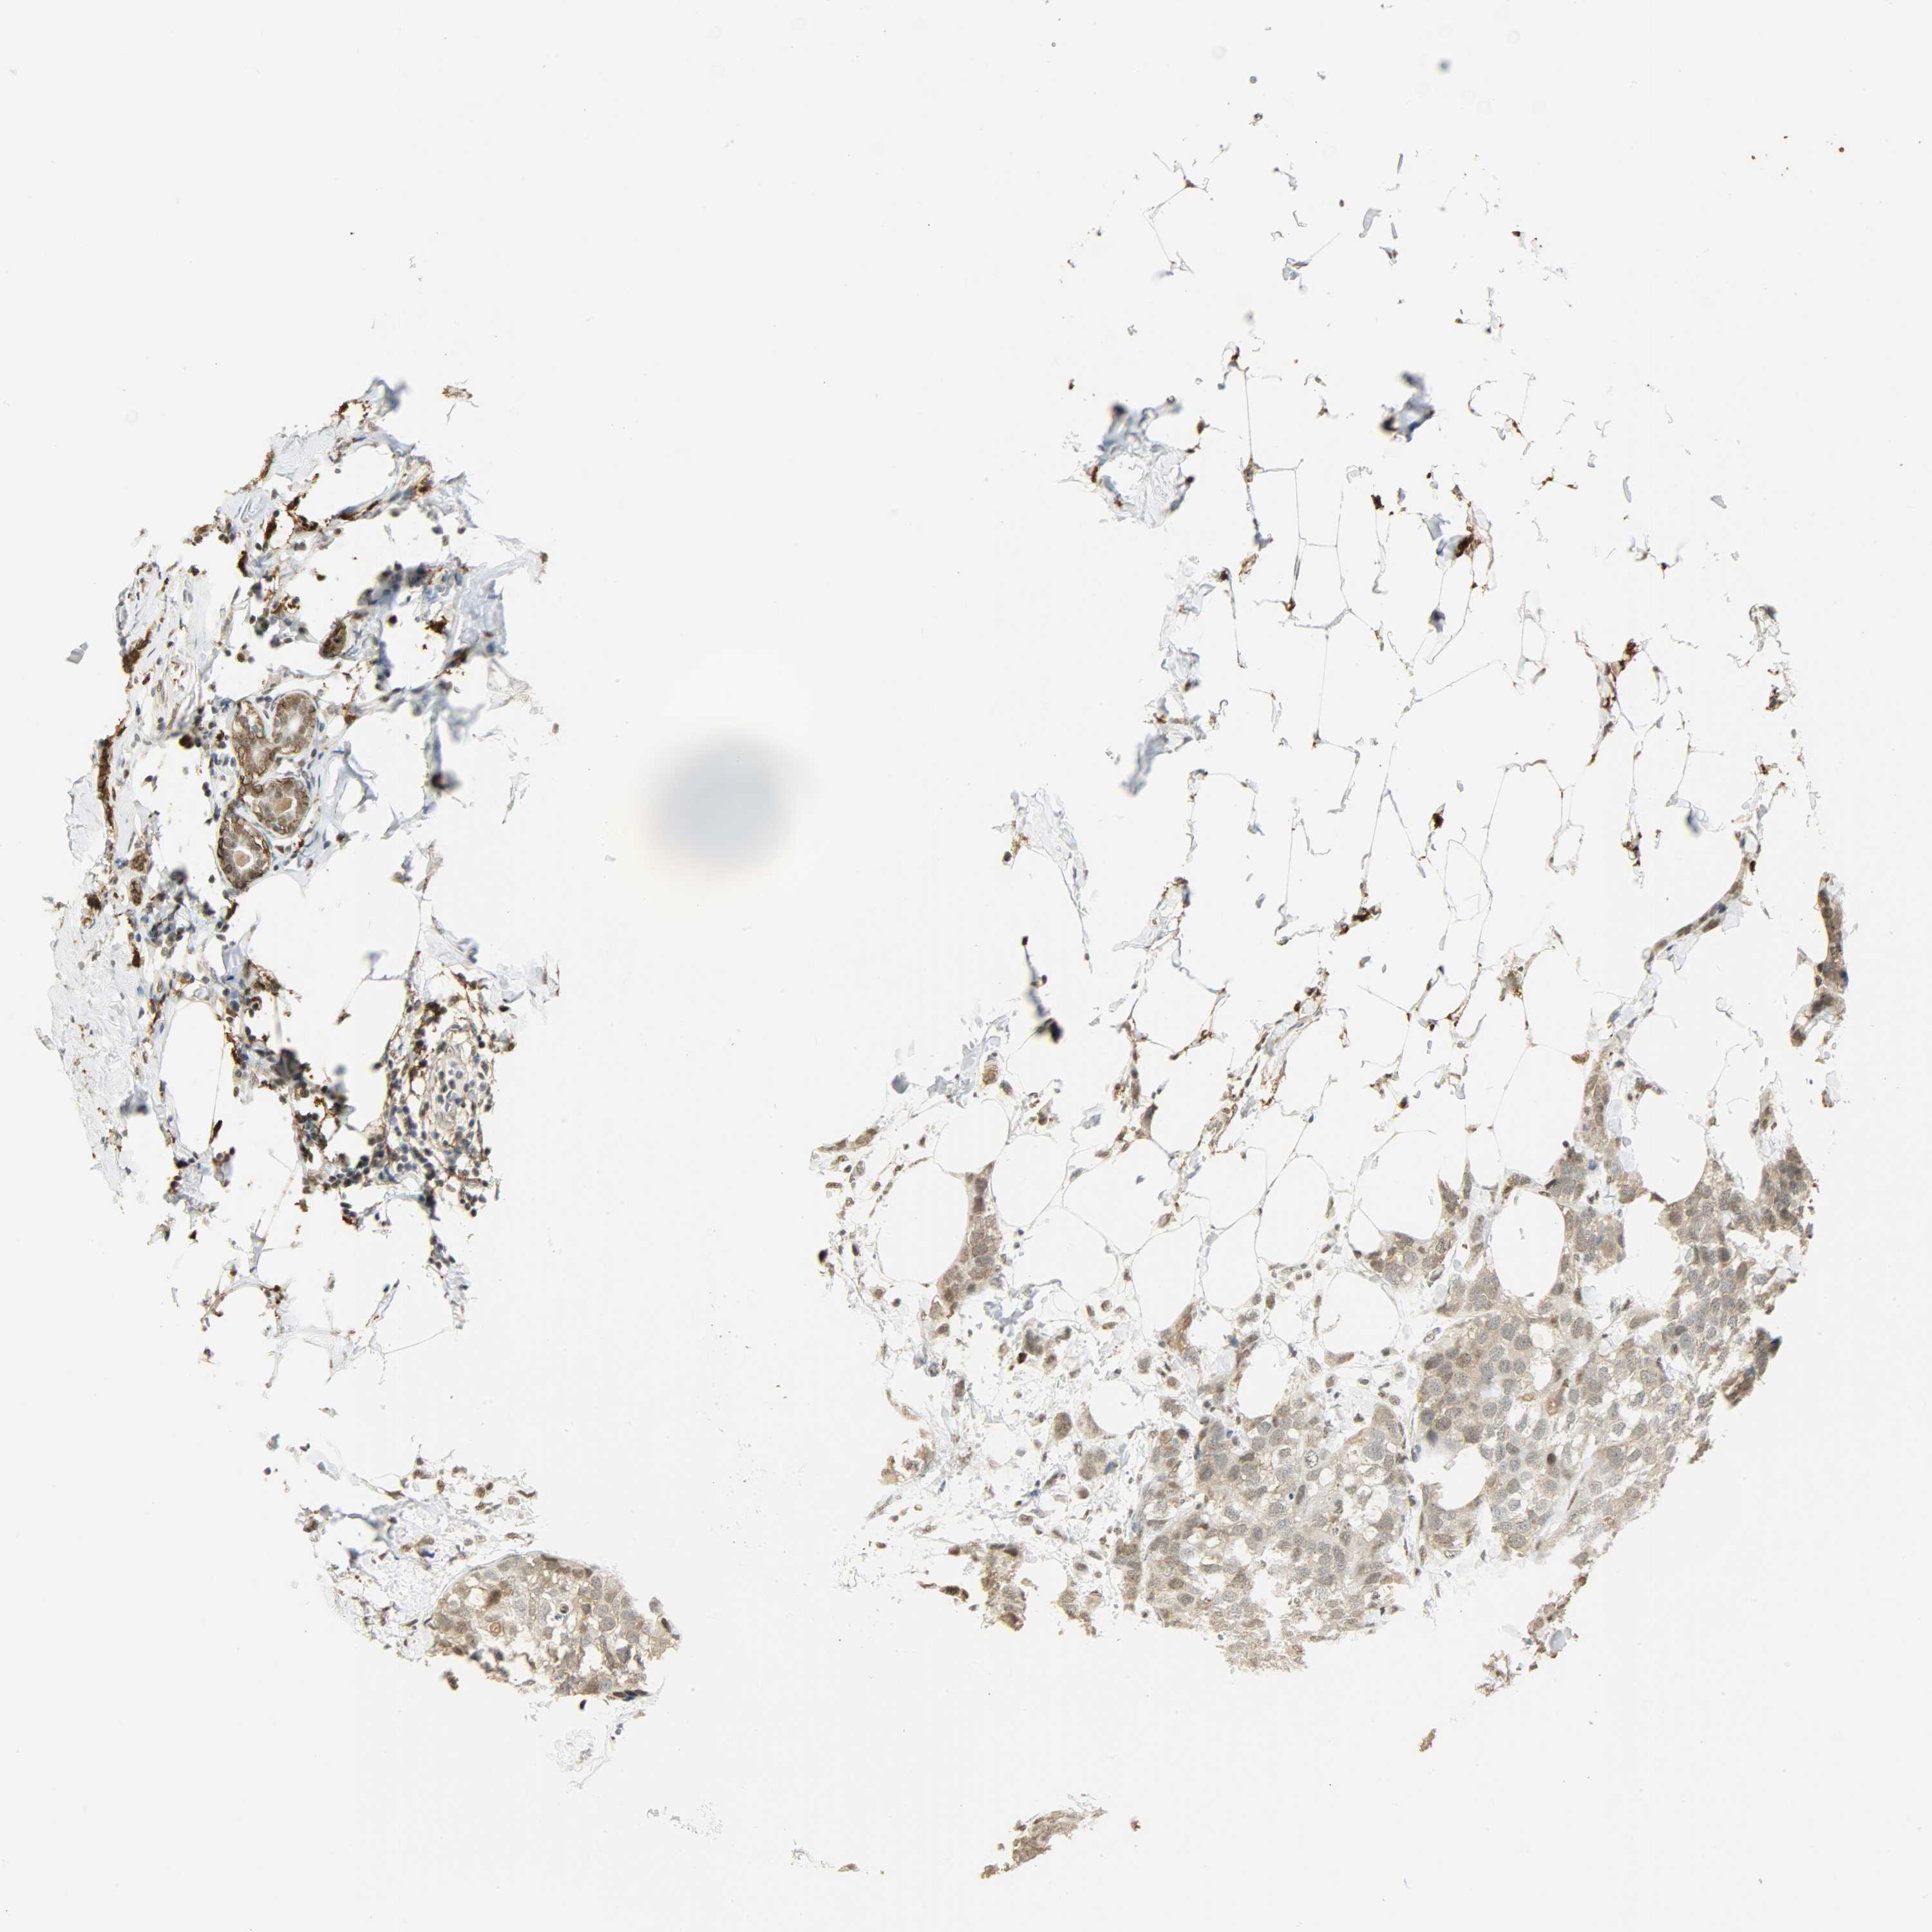

BRCA TCGA BRCA VALIDATION PROTEIN EXPRESSION

ANTIBODIES

AND

VALIDATION